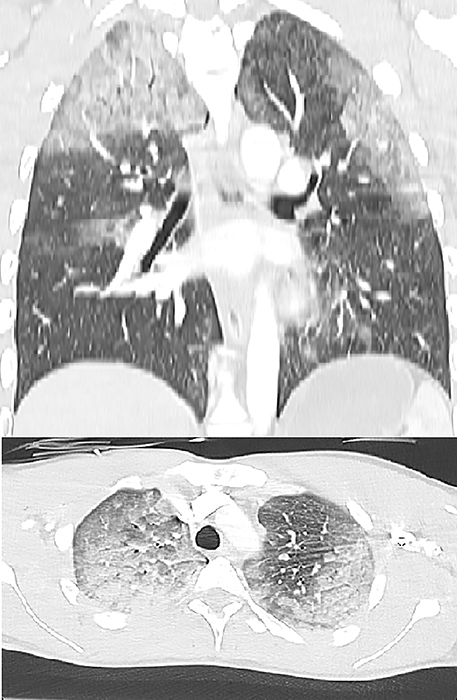

教学要点:神经源性肺水肿是脑外伤的一种罕见并发症,对于出现肺水肿的外伤患者,如果找不到其他原因,则应考虑神经源性肺水肿。

Teaching point: Neurogenic pulmonary edema is a rare complication of cerebral trauma and should be considered in trauma patients presenting with pulmonary edema when no other cause is found.